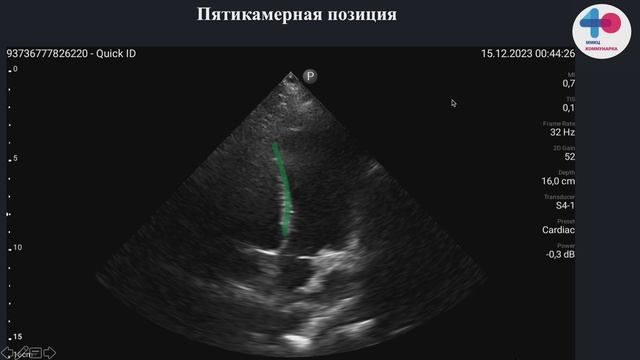

HOW TO Мониторинг волемического статуса - вариабельность VTI на выносящем тракте левого желудочка